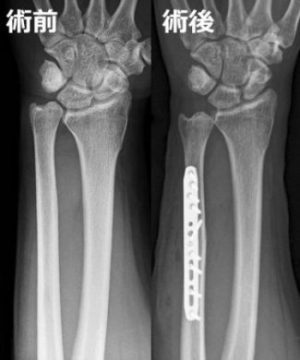

遠位橈尺関節の不安定性が強い場合や、保存的治療で十分な治療効果が得られない場合は手術療法が検討されます。橈骨よりも尺骨の方が長い場合は、尺骨短縮骨切り術【図1】が効果的で、損傷したTFCCに対する外科的処置としては(直視下・鏡視下)修復術【図2】、損傷から時間が経過した陳旧例には靱帯再建術【図3】が行われます。

【図1】尺骨短縮骨切り術の術前・後の単純X線像

相対的に長い尺骨を切って短縮し、プレートで固定します。